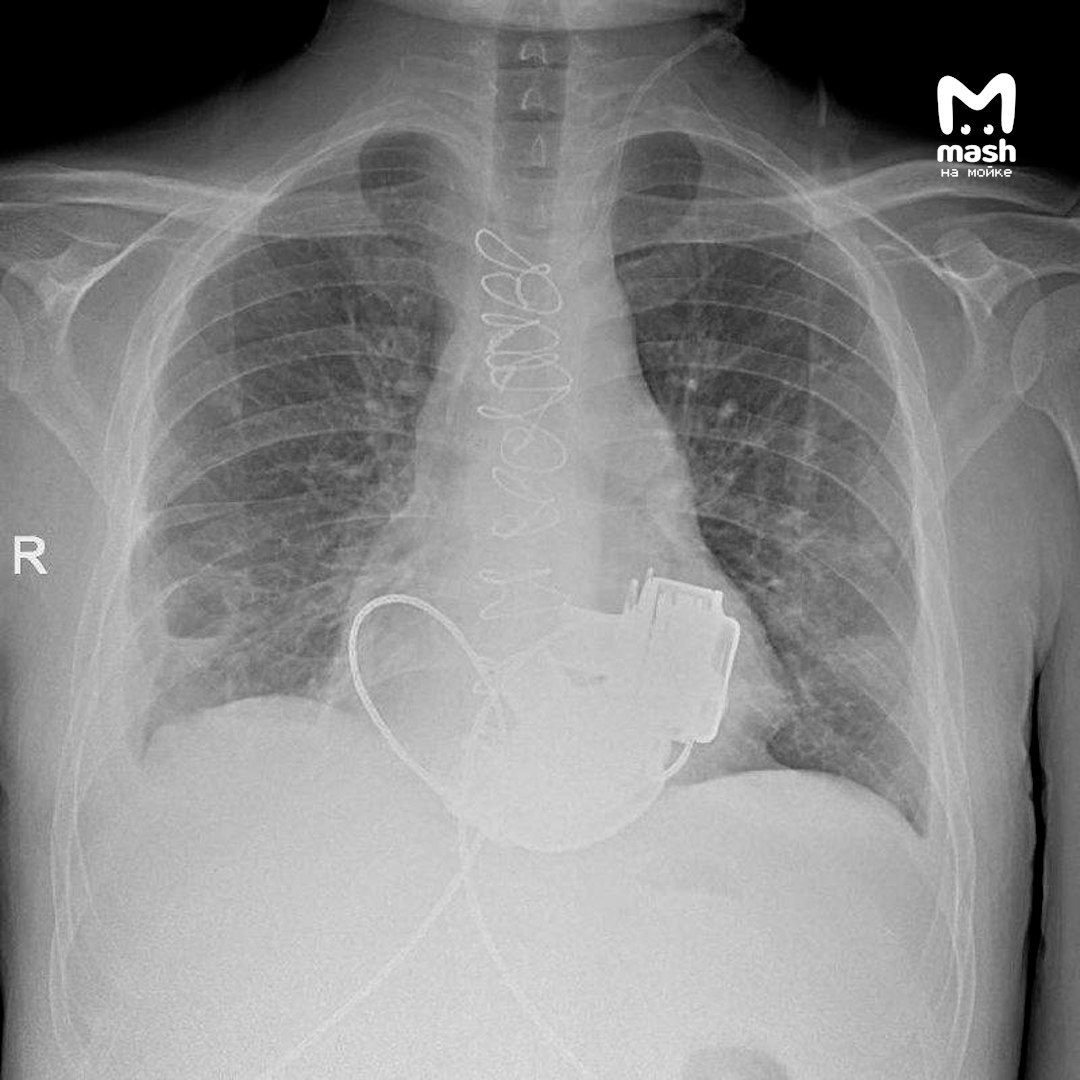

Самым сложным стала синхронизация работы двух устройств между собой. Из-за особенностей вмешательства у Антона теперь невозможно измерить пульс и давление, потому что импланты создают ламинарный (не пульсирующий) кровоток. Мужчина заряжает своё механическое сердце от двух аккумуляторов, зарядки хватает на 17 часов.